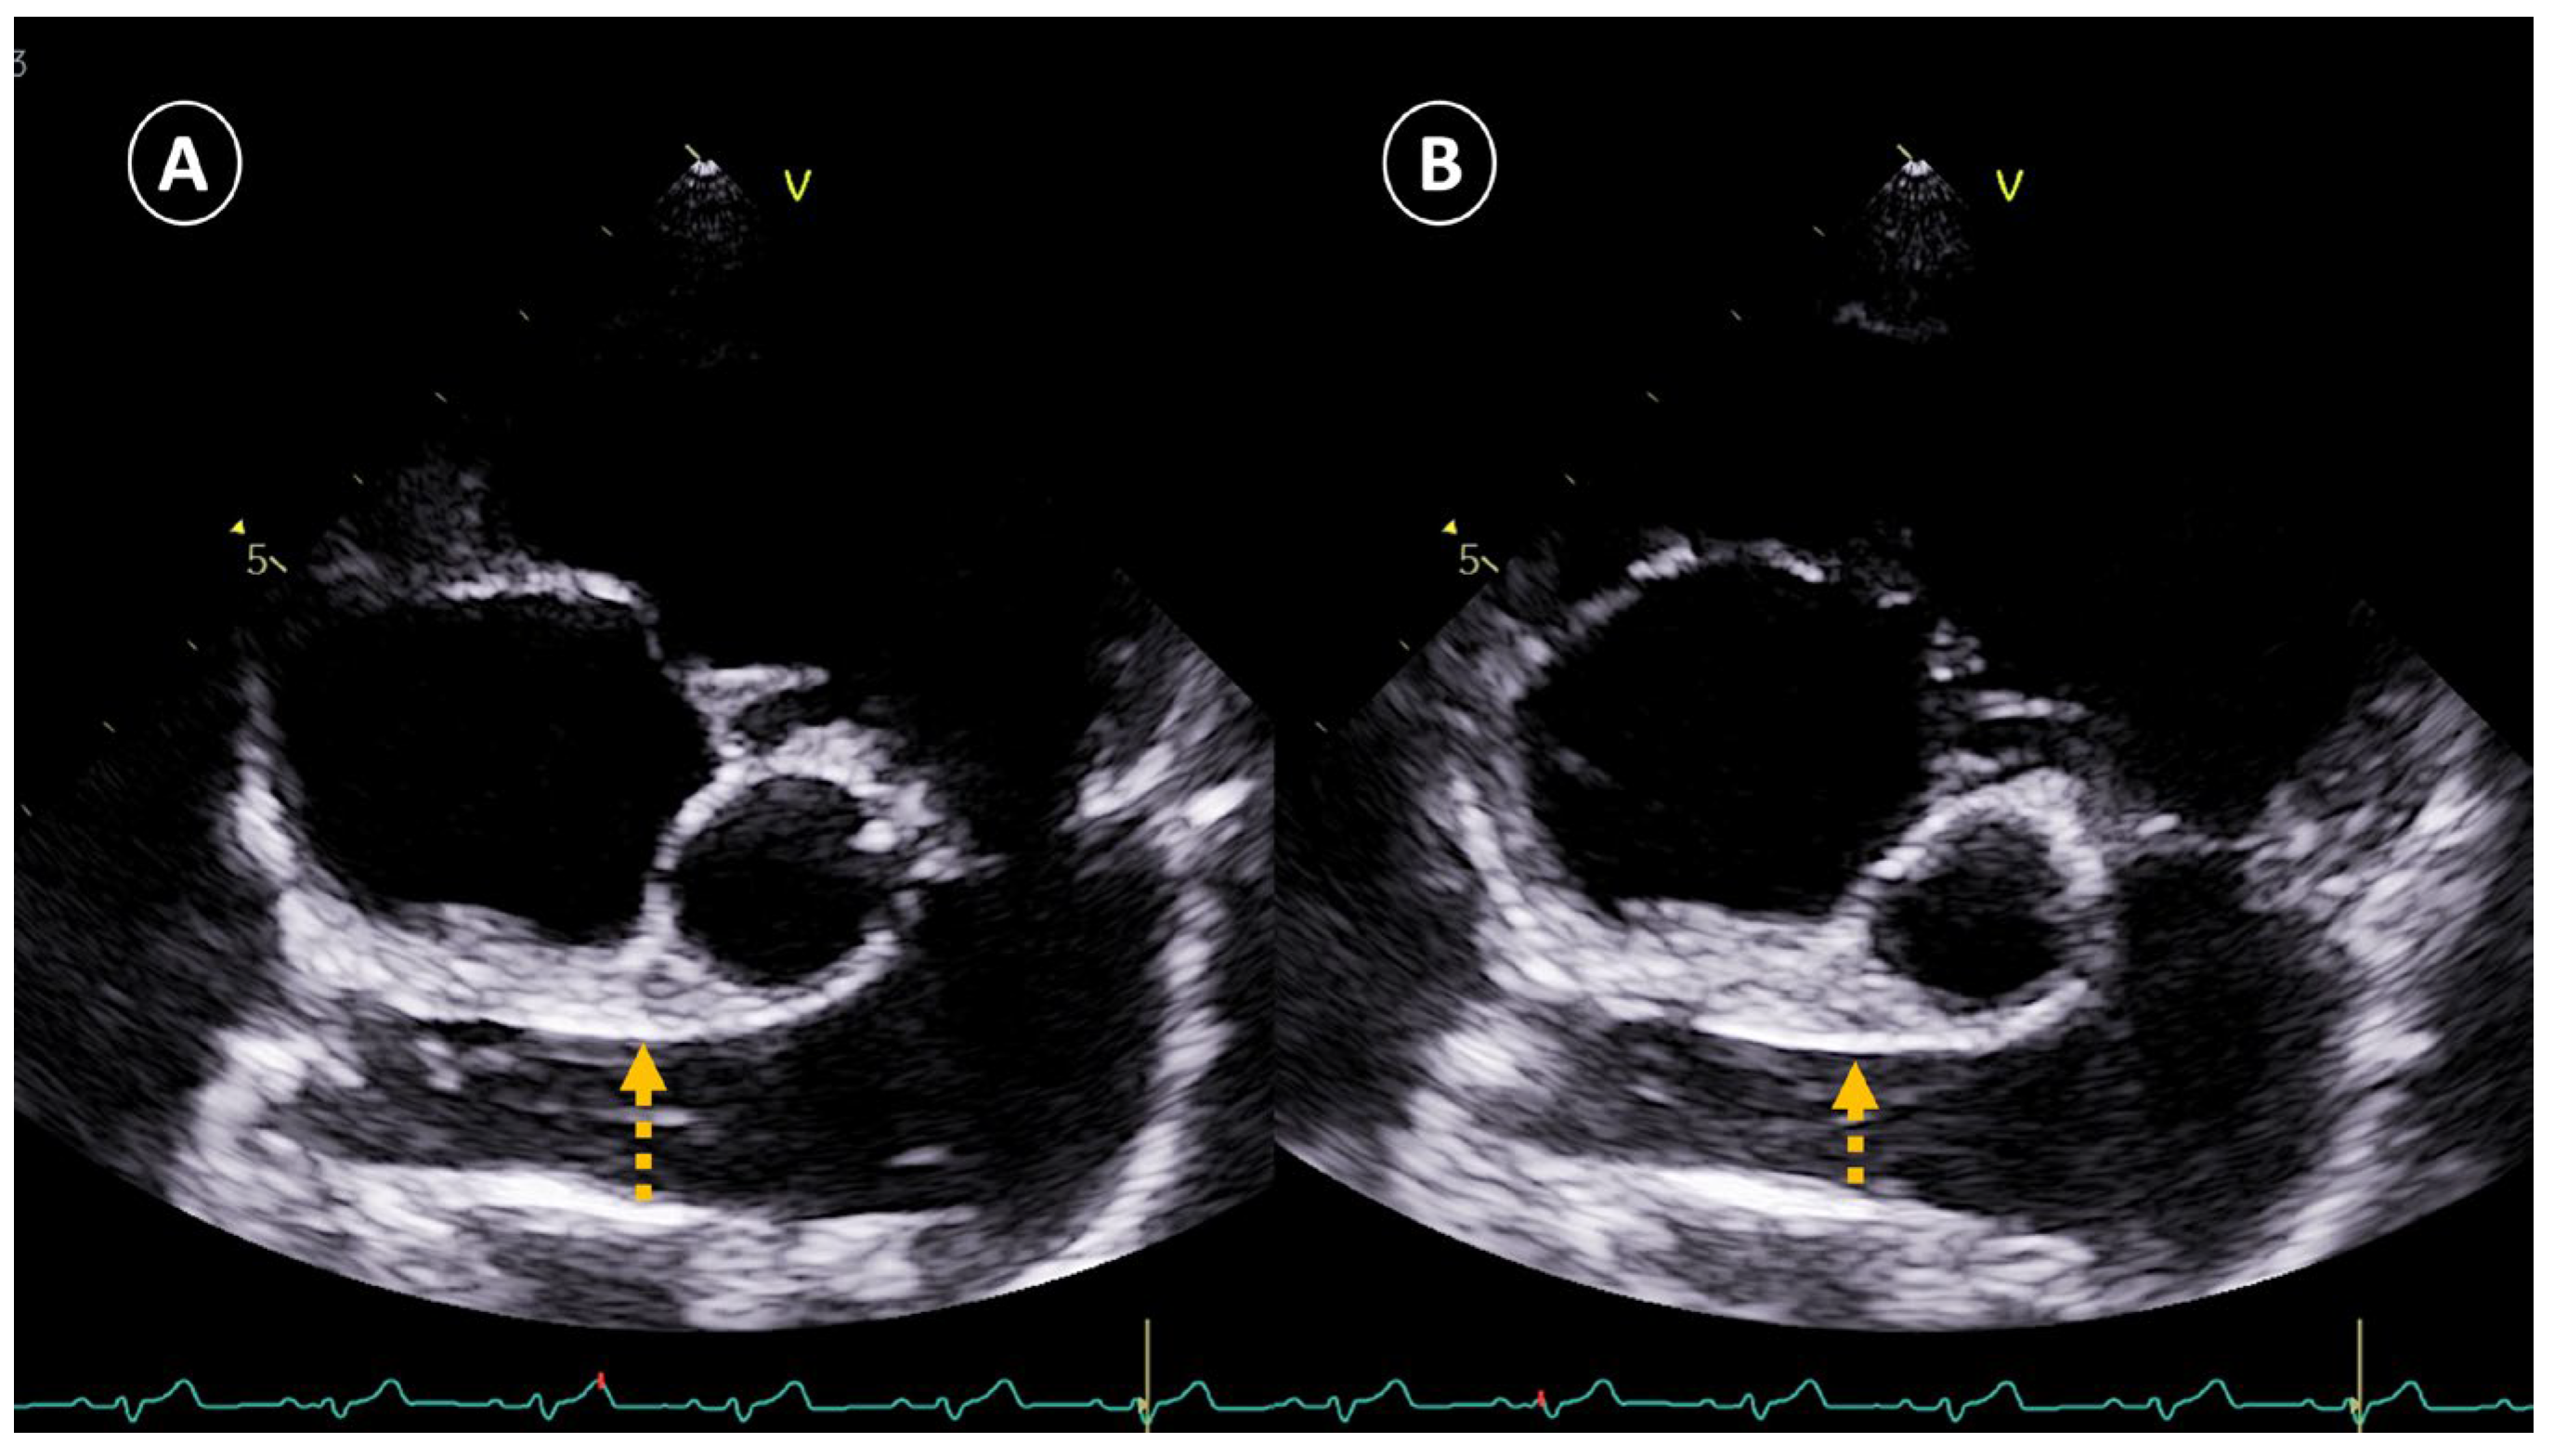

The determination of the presence of PH was based on the two different methods of obtaining the RPADi through the use of echocardiographic M-mode and 2D mode, being a value < 30% correlated in both cases with the presence of moderate or severe PH (>50 mmHg) [8,11]. To determine the RPADi using the Visser et al., method [11], the right parasternal short-axis view was applied at the level of the pulmonary trunk bifurcation, clearly observing the progression of the right and left branches. An adequate two-dimensional image with direct visualization of the longitudinal axis of the right pulmonary artery was obtained in all cases. The minimum diastolic and maximum systolic internal diameters were measured with the “trailing edge to leading edge” (te-le) method, using the same location of the right pulmonary artery (RPADVisser). Special care was taken to take measurements of the farthest portion, avoiding including the aorta (Ao) in the image (Figure 1). On the other hand, the determination of the RPADi using the Venco et al. method [8] was based on the right parasternal long-axis view of four cardiac chambers. M-mode was used in this case on the transverse axis of the right pulmonary artery when the left atrium, and pulmonary artery and vein were accurately observed. The right pulmonary artery diameters were measured using the “leading edge to leading edge” (le-le) measurement convention (RPADVenco) (Figure 2). In both cases, systolic diameter was measured at the maximum (T wave) and diastolic diameter at the smallest (Q wave) dimensions. The RPADi was calculated as the percentage difference in right pulmonary artery diameter in systole and diastole, using the following formula: RPADi = [(RPAmax − RPAmin)/RPAmax] × 100, as previously described [10].

Figure 1.

Representative image of the right pulmonary artery distensibility index (RPADi) measurement using the method of Visser et al. [10] in a dog with heartworms and pulmonary hypertension. The right parasternal short-axis view was used at the level of the pulmonary trunk bifurcation. An adequate two-dimensional image with direct visualization of the longitudinal axis of the right pulmonary artery was obtained. Systolic diameter (A) was measured at the maximum dimension (T wave), and diastolic diameter (B) at the smallest dimension (Q wave). Internal diameters were measured with the “trailing edge to leading edge” method, using the same location of the right pulmonary artery.